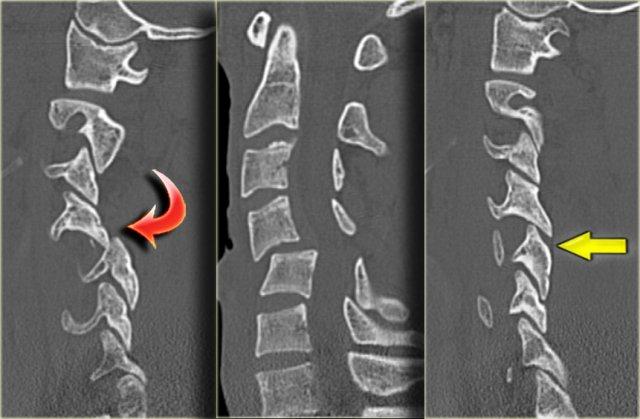

Các dấu hiệu bao gồm:

- Các mảnh xương nhỏ tách ra từ mặt khớp trên và dưới

- Khoang gian gai rộng ra tại C5-6

- Sưng nề mô mềm ở mức này về phía sau

- Hẹp nhẹ khoang đĩa đệm tại mức C5-6.

Các dấu hiệu CT này rất tinh tế và dường như không tương xứng với vấn đề thần kinh.

Trong trường hợp như vậy, MRI là bước tiếp theo cần thực hiện.